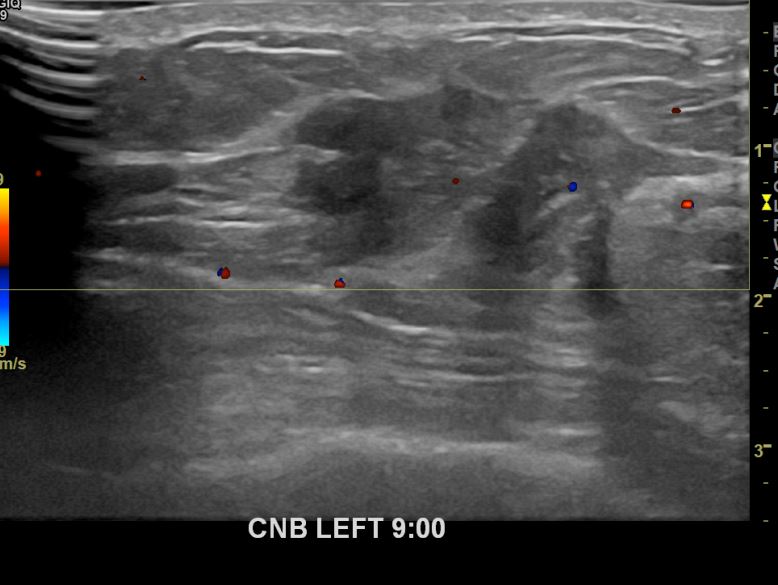

아산유외과개원후 666번째 유방암진단

상기환자 외부검사상 이상소견으로 내원하신 40대여성으로 좌측에 의심스러운혹 조직검사시행해 유방암 진단되었습니다